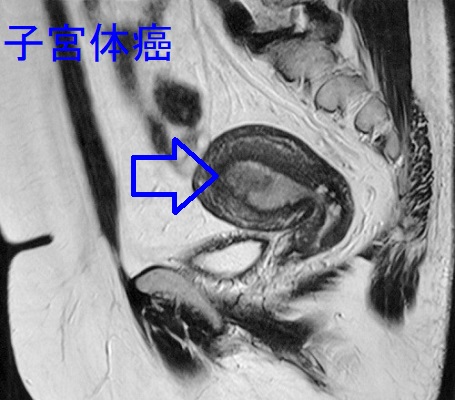

高エストロゲン血症は乳癌・子宮内膜がん(子宮体癌)の原因だが甲状腺分化癌(乳頭癌・濾胞癌)にも関与。子宮内膜がん(子宮体癌)と甲状腺癌(重複癌)・腺腫様甲状腺腫をおこす遺伝病はコーデン(Cowden)症候群、ポイツ・ジェガーズ症候群、遺伝性非ポリポーシス大腸がん(リンチ症候群)、家族性腺腫様甲状腺腫。エストロゲン受容体・プロゲストロン受容体(ER/PgR)を持つ篩(ふるい)型[モルラ(渦巻き)型]甲状腺乳頭癌も存在。子宮体部神経内分泌腫瘍は極めてまれで悪性度が高い。子宮平滑筋肉腫の甲状腺転移は非常にまれで、甲状腺原発の平滑筋肉腫と鑑別。

子宮内膜がん(子宮体癌)は、高エストロゲン血症が原因となり発症します。

子宮体部神経内分泌腫瘍は、極めてまれです。悪性度が極めて高く、